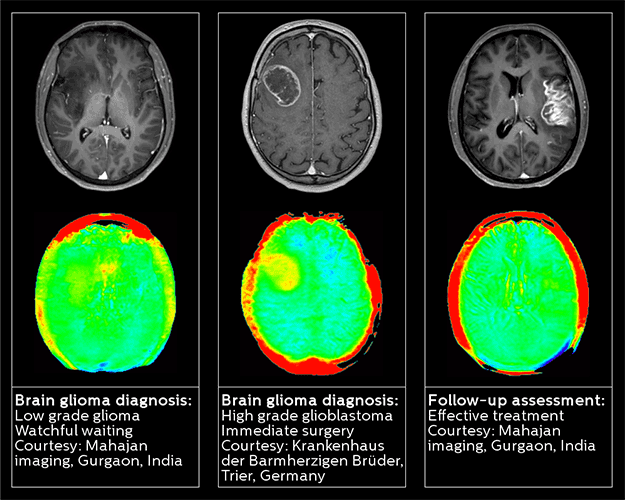

Enhanced diagnostic confidence in Neuro-oncology   Establishing the diagnosis of a brain tumor is not always straightforward. MRI is the gold standard but not reliable enough for tumor follow up.1 The presence of contrast enhancement can confuse the diagnosis of malignant brain tumors, and therefore differentiating low- from high-grade gliomas can prove to be a challenge for radiologists. With three out of five radiologists finding brain tumor diagnosis “challenging” to “very challenging,” it’s evident that this is an area of unmet need; there is also a vital demand for methods that can detect response to therapy at early follow-up times.2   Philips 3D APT (Amide Proton Transfer) is a unique, contrast-free, brain MR imaging method, designed to help radiologists differentiate between low-grade and high-grade gliomas. This technology works by using the presence of endogenous cellular proteins to produce an MR signal that directly correlates with cell proliferation, a marker of tumor activity.    1 Neurology. 2002 Sep 24;59(6):947-9. 2 Cancer Manag Res. 2014; 6: 149–170.

By using Philips 3D APT, radiologists can now make a confident diagnosis and more confidently assess the pathway and urgency of a patient’s treatment plan.